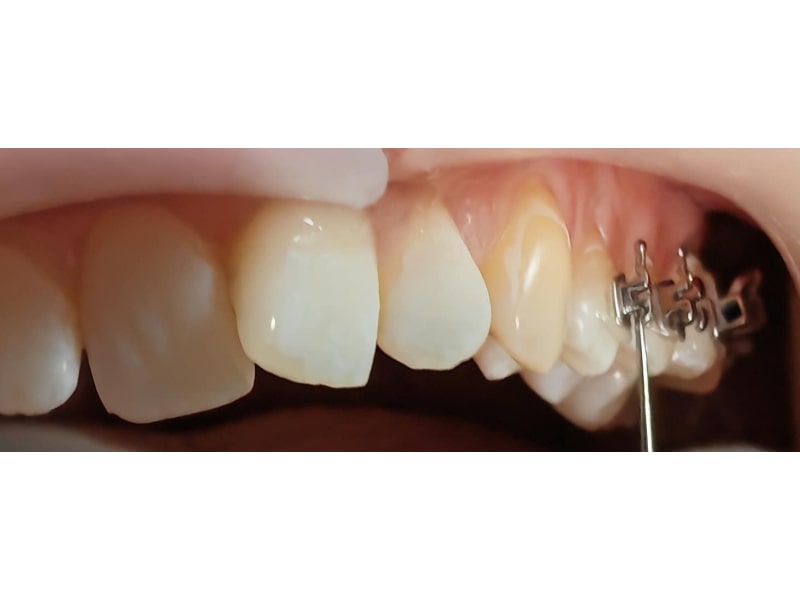

Ortodonție